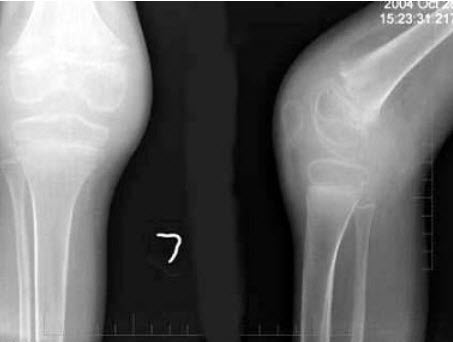

76、单项选择题

男,13岁,运动后膝关节疼痛,结合图像,最可能的诊断是()

A.正常影像

B.动脉瘤样骨囊肿

C.骨软骨瘤

D.成骨细胞瘤

E.骨样骨瘤